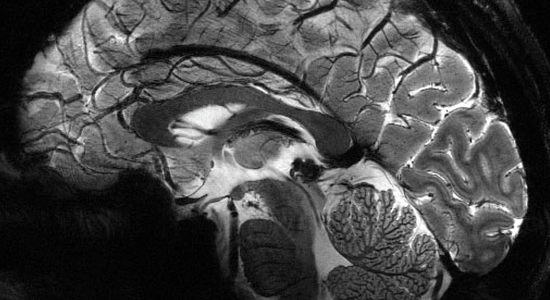

Concours photo neurosciences 2019

PHOTO-NEUROSCIENCES est un concours de photographie organisé par l’Association Auver-Brain dans le cadre de la 21ème édition de la Semaine du Cerveau à Clermont-Ferrand (08-15 mars 2019)

Thème du concours : « Le cerveau champion ».

L’équipe de France de football a gagné la Coupe du Monde et nous avons tous été plus ou moins touchés par la ferveur collective suscitée par cette victoire. Lors des compétitions sportives, qu’on soit acteur ou spectateur, gagnant ou perdant, notre cerveau nous fait vivre des émotions variées : joie, jubilation, fierté, tristesse, colère, déception, … Comment réagit le cerveau d’un gagnant ? Et celui d’un perdant ? Quelles sont les sensations ressenties par les supporters, la famille, les amis, … ? Le but de ce concours est de rapprocher les neurosciences et le grand public à travers votre vision artistique et esthétique, suggérée grâce à des images qui illustrent le thème du concours « Le cerveau champion ». C’est à vous de nous faire vibrer avec vos oeuvres, qui feront l'objet d'une exposition du 5 au 22 mars 2019.